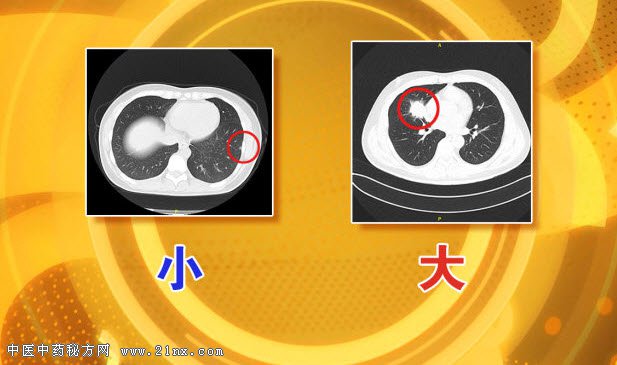

图:肺部结节大与小 这其中,大家普遍认为不好的多发结节、不光滑结节,是不是一定预示着肺癌的到来?预防肺癌,医生在饮食上又有什么建议?节目中将为您解答。 20160702养生堂视频和笔记:李单青,肺癌,肺癌检查,肿瘤标记物 |